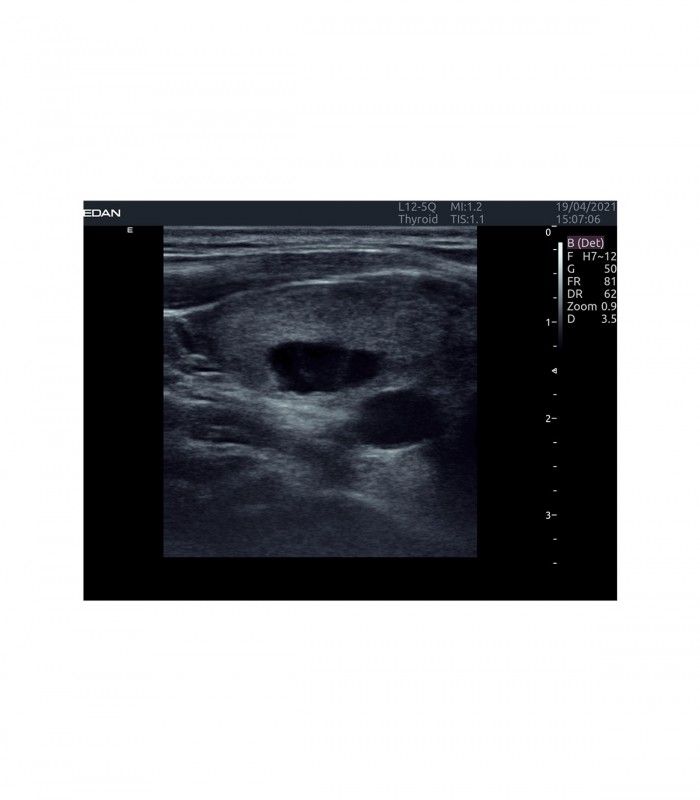

Il est polyvalent dans de nombreux domaines d’applications tels ; obstétrique, gynécologie, urologie, musculo squelettique, cardiologie, vasculaire, abdominal, etc.

L’AX4 affiche une image claire et précise dans les différents modes grâce à de multiple technologies de traitement de l’image.

L’Imagerie Tissulaire Adaptative (TAI) ajuste automatiquement en temps réel de nombreux paramètres, dès la pose de la sonde sur le patient, afin d’afficher la meilleure qualité d’image, permettant ainsi au praticien de poser un diagnostic plus rapidement.

- eSRI : imagerie adaptative à réduction de Speckle

- ASCI : imagerie à corrélation spatiale adaptative

- Zoom digital pour limiter les pertes de détails